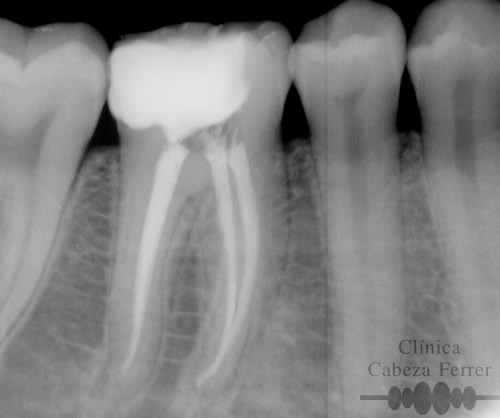

| Antes | Después |

En primer lugar se explora la pieza y se realiza un estudio radiológico. Si es necesario se pone anestesia local y se aísla en diente para mantenerlo limpio y seco durante el tratamiento. A continuación con el instrumental adecuado se realiza un orificio en la corona del diente y a través de él, mediante unos pequeños instrumentos llamados LIMAS, se extrae la pulpa. Posteriormente la cámara pulpar y los conductos radiculares se limpian, se esterilizan, se rellenan y se sellan herméticamente. Con un control radiológico se comprueba que el tratamiento se ha realizado correctamente. Ahora es el momento de reconstruir la anatomía del diente y si es necesario recubrirle con una corona para evitar su posterior fractura. En la mayoría de los casos, la endodoncia se realiza en una sola sesión.

La endodoncia rotatoria avanzada es una novedosa técnica de instrumentación mecanizada que se realiza con un tipo de limas especiales de níquel-titanio. El auge del níquel-titanio surgió en la década de los sesenta, al ser utilizado por la NASA, principalmente en la fabricación de antenas de naves y satélites espaciales. Es este material, el que impulsa el desarrollo de los sistemas rotatorios en endodoncia. Estos instrumentos tienen la característica de de ser muy flexibles, por lo que pueden trabajar dentro de los conductos radiculares impulsados por un motor de baja velocidad, ejecutando una rotación de 360º hasta en los conductos curvos. De esta manera se combina la instrumentación manual convencional con la mecanizada consiguiendo así un resultado final con alta precisión, mejor limpieza, irrigación y terminación de los conductos, menos fracasos y unas restauraciones más duraderas.